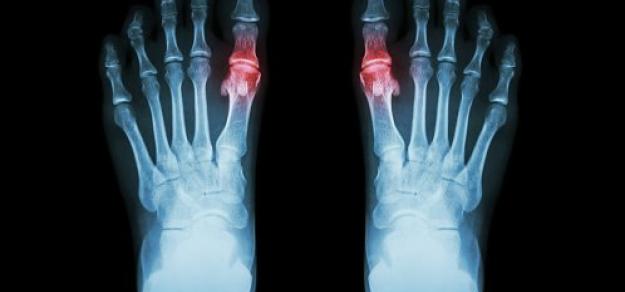

En pacientes con gota y sin enfermedad coronaria, el uso prolongado de alopurinol protege contra el primer síndrome coronario agudo (SCA) en comparación con los no usuarios. Por el contrario, los iniciadores del alopurinol, que posiblemente tenían más inflamación sistémica, tenían un mayor riesgo de SCA por primera vez en comparación con los usuarios a largo plazo. BMJ Open, 27 de febrero de 2025

En este estudio de cohorte poblacional, los pacientes diabéticos de tipo 2 tratados con metformina que iniciaron un inhibidor de SGLT-2 tuvieron menor frecuencia de crisis gotosas que aquellos a los que se agregó sulfonilureas. Estos resultados ayudan a guiar la selección de la terapia hipoglucemiante en pacientes con diabetes tipo 2 con riesgo de gota o que ya la padecen. JAMA Internal Medicine, 15 de abril de 2024.

En este ensayo clínico aleatorizado una intervención dietética intensiva fue segura y redujo eficazmente el peso corporal en personas con obesidad y gota, pero la pérdida de peso no se tradujo directamente en efectos sobre el nivel de uricemia, la fatiga, el dolor ni las exacerbaciones agudas de la gota. Arthritis & Rheumatology, enero de 2024.

En este estudio retrospectivo de pacientes con antecedentes de gota, los niveles de urato sérico al inicio del estudio se asociaron con el riesgo de brotes de gota posteriores y las tasas de hospitalización por gota recurrente. Estos hallazgos respaldan el uso de un nivel inicial de urato sérico para evaluar el riesgo de gota recurrente durante casi 10 años de seguimiento. JAMA, 6 de febrero de 2024.

En este estudio observacional se comparó el inicio de alopurinol para la gota acompañado de profilaxis con colchicina o con AINE versus alopurinol sin profilaxis asociada. Los eventos adversos fueron más comunes cuando se inició alopurinol con profilaxis, particularmente la aparición de diarrea con el uso de colchicina. Otros eventos fueron poco comunes, lo que brinda tranquilidad a los pacientes y a los médicos para permitir la toma de decisiones compartida. Annals of the Rheumatic Diseases, octubre de 2023.